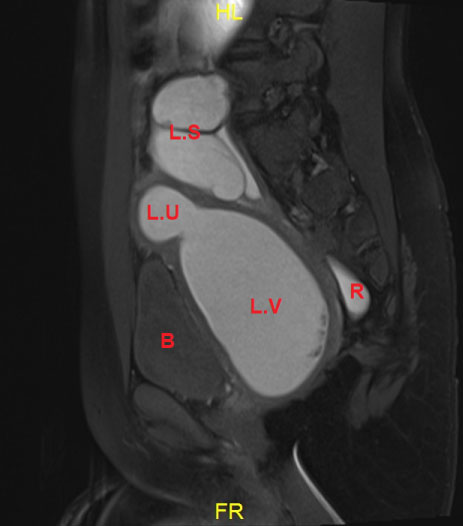

Pelvic MRI showed uterus Didelphis with two hemi-uteri and two hemi-vaginas, the left hemi-vagina was blind, (Figure 1), left hematometro-colpos, and hematosalpinx overlying the dome of the urinary bladder (Figure 2 and Figure 3), Also, it showed left renal agenesis (Figure 4).

Figure 1: MRI image transverse cut.

LU: Left uterus horne, Dilated; LV: Left vagina, Dilated; RU: Right uterus horne; RV: Right patent hemivagina. View Figure 1